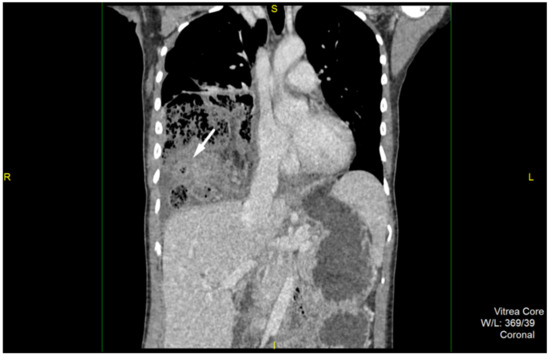

2. Case Report